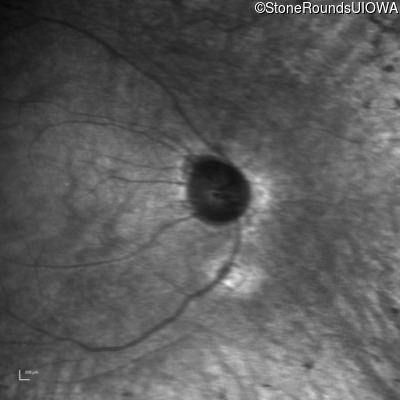

Infrared Fundus Photograph - Right - 20/70 -2

Exemplar